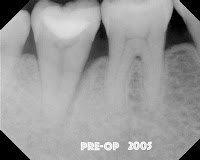

This most recent case is a periodontist who came to our practice. I originally did the root canal in 2005. It had an odd lateral lucency – which might be suggestive of a root fracture. We completed root canal without finding a fracture.